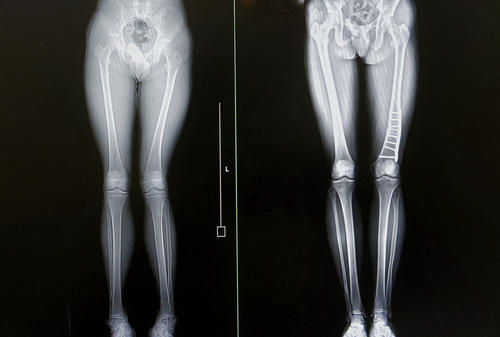

Фотогалерея

- мониторирование эффекта хирургического вмешательства, выполненная операция;

- оценка срастания переломов;

- отслеживание динамики имеющихся заболеваний;

- мониторинг успешности терапии.